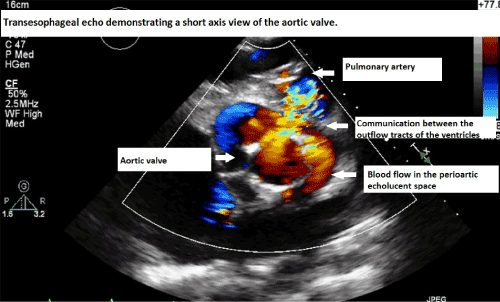

| Figure 1: Parasternal long axis view of transthoaracic echocardiogram demonstrating the plane of the left ventricular outflow tract, the dehisced aortic valve is seen to be displaced superiorly. Note the echolucent space around the point of dehiscence. |